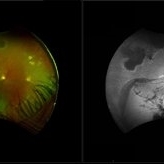

A 34-year-old man presented with a right intraocular foreign body after hammering a carbon-steel chisel 12 hours after injury. CT orbits showed a 3-mm hyperattenuating foreign body within the right globe, centered in the vitreous cavity. BCVA was 20/40. Anterior segment examination revealed a 2.8-mm scleral laceration. DFE demonstrated a metallic IOFB, a superior air bubble, superior commotio retinae, and Berlin’s edema involving the macula.

Photographer: Nikhil Das, Saint Louis University School of Medicine

Imaging device: iPhone

Condition/keywords: intraocular foreign body, iofb, metallic foreign body, scleral laceration